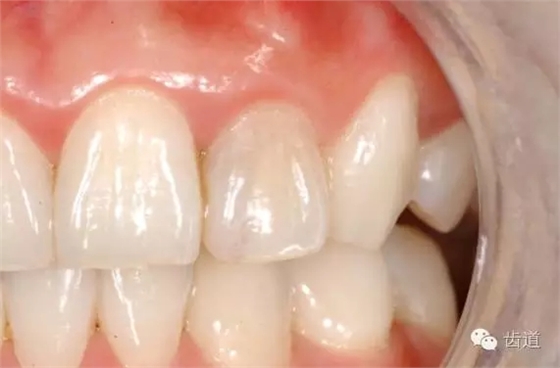

七)美觀(esthetics):

位置、形態(tài)、排列、色彩與鄰牙及整個牙列協(xié)調(diào)